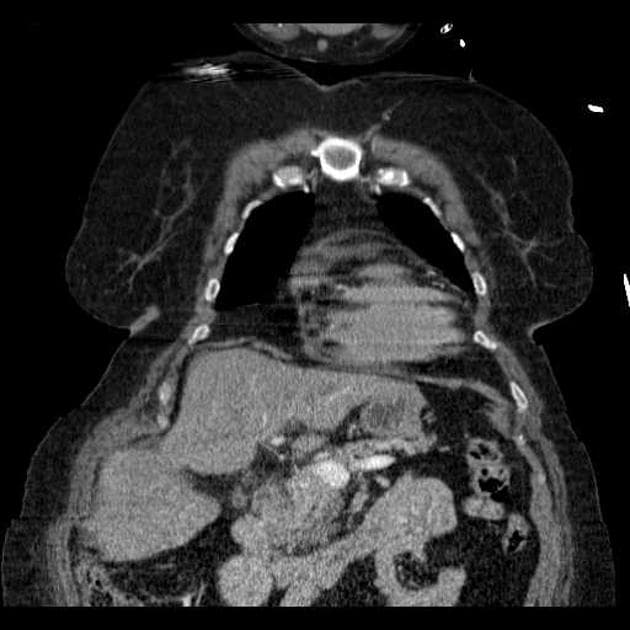

Hai lòng mạch riêng biệt với sự khác biệt về cường độ tín hiệu, tạo nên hình ảnh "động mạch chủ hai lòng" (double barrel aorta) được quan sát thấy trên các dãy ảnh MRCP.

Chụp cắt lớp vi tính động mạch chủ (CTA) xác nhận tình trạng bóc tách động mạch chủ type B (Stanford B). Vị trí bóc tách bắt đầu ở đoạn động mạch chủ phía dưới (distal) gốc động mạch thân cánh tay đầu (brachiocephalic trunk), kéo dài đến động mạch chậu chung trái.

Lòng giả (false lumen) lan vào động mạch thận trái, gây giảm tưới máu (reduced perfusion), phù hợp với hiện tượng giảm tăng quang của thận trái so với bên đối diện.

Ghi nhận hẹp đáng kể (significant stenosis) ở gốc động mạch thân tạng (coeliac trunk).

Động mạch mạc treo tràng trên (SMA) được làm đầy bởi lòng thật (true lumen), không thấy hẹp đáng kể.